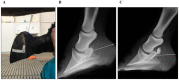

The analgesic specificity of navicular bursa (NB) anesthetic infiltration is still questionable. The study aimed to determine the mechanical nociceptive threshold of non-specific analgesia in the dorsal lamellar stratum, as well as in the sole, coronary band, and heel bulbs of the hoof, after navicular bursa anesthetic infiltration. Six healthy horses with no clinical or radiographic changes of the digits and no communication between the NB and the distal interphalangeal joint, were used. After random selection, the NB of one of the forelimbs was infiltrated with 2% lidocaine and the contralateral one with lactated ringer's solution. Contrast was added to confirm radiographic infiltration. The mechanical nociceptive threshold was determined using a portable pressure dynamometer, before and at various times after the infiltration, in 10 points of the hoof. The effects of time and treatment were verified by ANOVA (P<0.05). There was no statistical difference in the values of the mechanical nociceptive threshold (P>0.05) in all regions evaluated. However, in one of the six hooves that receives lidocaine, complete absence of response to the painful stimulus (maximum force of 6 Kg over an area of 38.46 mm2, for a maximum of 4 seconds) was observed in the dorsal lamellae between 30 and 60 min after infiltration. In conclusion, lidocaine infiltration of NB did not promote significant increases in the nociceptive threshold of the sole, coronary band, bulbs of the heel and dorsal lamellae clinically healthy horses. However, the occurrence of analgesia in one of the six hooves subjected to NB anesthesia indicates that the technique may not be fully specific in few horses.